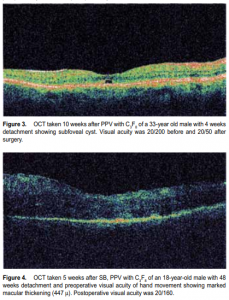

4 weeks after their surgery, 10 at between 4 and 8 weeks, and the rest (13) after 8 weeks. ANOVA comparing these three groups with respect to postoperative VA showed no significant difference (f = 0.33, p < 0.72). The average macular thickness was 254 ± 60 µ (range, 204 to 447 µ; median, 250 µ). There was a strong positive correlation between macular thickness and postoperative logMAR VA (r = 0.35, p < 0.02, Table 4), which implied that the thicker the macula, the worse the vision (higher logMAR value). The OCT images obtained showed various retinal abnormalities (Figures 1 to 4). Nineteen (49%) patients exhibited pockets of SRF (Figure 1), 6 (15%) had foveal thinning, 5 (12%) had macular hole (Figure 2), and 1 each had foveal cyst (Figure 3), cystoid macular edema (CME), and epiretinal membrane. Of the 19 patients with pockets of SRF, 14 (74%)

underwent SB with external drainage, 3(14%) had pneumatic retinopexy, and 2 (10%) were post-scleral buckling and had vitrectomy and C3 F8 (Table 5). Odds-ratio analysis involving the presence or absence